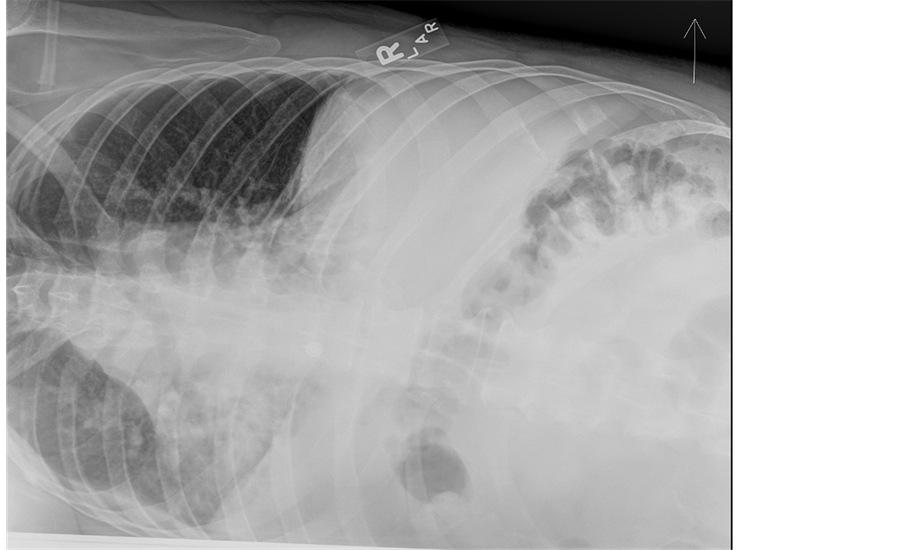

In addition to the increased work of breathing, his pulmonary exam was remarkable for bibasilar crackles. An electrocardiogram showed normal sinus rhythm with normal axis and intervals. Basic chemistry labs including a cardiac panel were with normal values save a serum creatinine of 1.22 mg/dL. Inflammatory markers were expectedly elevated with a sedimentation rate of 31 mm/h and a C-reactive protein value of 33 mg/L. A complete blood count with differential was normal. An influenza panel was negative for influenza A and B (later verified by antigen testing). An anterior chest ray revealed hypoinflated lungs with bibasilar parenchymal consolidation and associated bilateral pleural effusions (Figure 1) which were confirmed by a lateral decubitus image (Figure 2). Note, the presence of an effusion is evident by increased opacification of the compressed left lung with concomitant aeration of the right lung.

Figure 2. The figure is a left lateral decubitus radiograph. Decubiti radiographs are useful in assessing the volume of an effusion. The presence of an effusion is evident by increased opacification of the compressed left lung with concomitant aeration of the right lung.